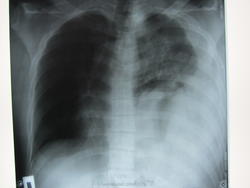

Пол пациента: Мужской пол Тип патологии: Травма Область исследования: Грудная клетка и верхние дыхательные пути Методы исследования: Rg Молодой человек попал в ДТП. В итоге разрыв диафрагмы слева, эвентрация кишечника в левую плевральную полость . https://radiomed.ru/sites/default/files/styles/case_slider_image/public/user/12810/img_0484.jpg?itok=XIFvARKg https://radiomed.ru/sites/default/files/styles/case_slider_image/public/user/12810/img_0487.jpg?itok=oc4Y7inH ID:27003 Втр, 12/03/2013 - 22:08 #1 Almo Не на сайте Был на сайте: 1 неделя 6 дней назад Зарегистрирован: 28.09.2008 - 18:50 Публикации: 8302 R-граммы №2 и№3 архивные? Втр, 12/03/2013 - 23:14 #2 И.Бондаренко Не на сайте Был на сайте: 14 часов 10 минут назад Зарегистрирован: 13.09.2011 - 22:55 Публикации: 9213 Almo wrote: R-граммы №2 и№3 архивные? Нет. После операции. Разница в один день. Втр, 12/03/2013 - 23:16 #3 алкс Не на сайте Был на сайте: 10 лет 5 месяцев назад Зарегистрирован: 24.10.2012 - 22:55 Публикации: 2915 2 и 3 последние. Это классные хирурги на последних снимках. Страшное дело, можно было и ушиб написать по экстренке. А позвоночник ничего? Ср, 13/03/2013 - 08:42 #4 UZY Не на сайте Был на сайте: 7 лет 10 месяцев назад Зарегистрирован: 18.10.2011 - 17:04 Публикации: 54 Молодцы хирурги! Чт, 14/03/2013 - 20:35 #5 И.Бондаренко Не на сайте Был на сайте: 14 часов 10 минут назад Зарегистрирован: 13.09.2011 - 22:55 Публикации: 9213 алкс wrote: 2 и 3 последние. Это классные хирурги на последних снимках. Страшное дело, можно было и ушиб написать по экстренке. А позвоночник ничего? Позвоночник цел. Перелом дистального метафиза правой бедренной кости.

R-граммы №2 и№3 архивные?

Нет. После операции. Разница в один день.

2 и 3 последние. Это классные хирурги на последних снимках. Страшное дело, можно было и ушиб написать по экстренке. А позвоночник ничего?

Позвоночник цел. Перелом дистального метафиза правой бедренной кости.